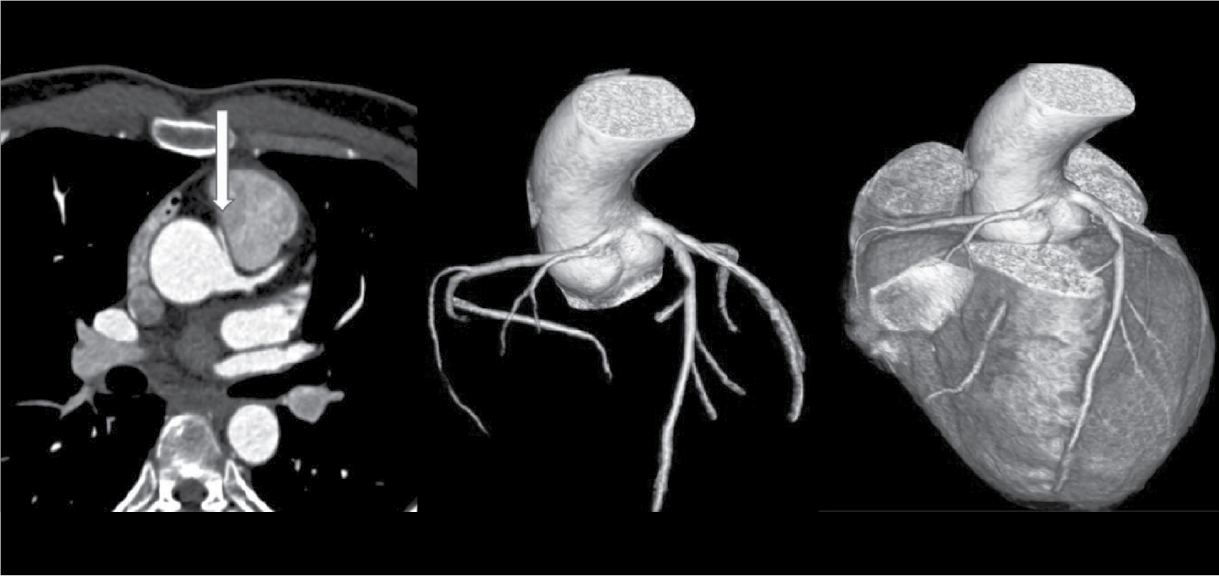

Figure 1. Two different patients of ‘high take-off’ of LCA in patient aged 61/M and RCA in patient aged 58/M.

At Nizam’s Institute of Medical Sciences (NIMS), Hyderabad, 770 patients underwent CT-conventional coronary angiography (CAG), on 128-slice single source MDCT (SOMATOM Definition AS ± SEIMENS) during the last 3 years (unpublished data). On analysis, coronary artery anomalies were found in 23 patients (3%). Their ages ranged from 25 to 82 years. Majority of the cases were in 51 to 60 years age group. Among them, 17 were males. The most common anomaly seen was high take-off of coronary arteries, seen in 10 cases. Of them, 2 were having high origin of right coronary artery (RCA) (Fig. 1), 7 were having high origin of left main coronary artery (LMCA) and one was having high origin of both coronary arteries with acute kink at the origin of RCA. Anomalous origin of coronary artery from opposite sinus was seen in 8 cases (Figs. 2-5). RCA from left coronary sinus with interarterial course between aorta and right ventricular outflow tract was seen in 5 cases. Anomalous origin of left coronary artery (LCA) from right coronary sinus with interarterial course between aorta and right ventricular outflow tract was seen in 2 cases. Anomalous origin of left circumflex artery (LCx) from right coronary sinus with retroaortic course was seen in 1 case (Fig. 6). Separate ostia for left anterior descending artery (LAD) and LCx was noted in 3 patients (Figs. 7 and 8). Shepherd crook deformity of proximal segment of RCA was seen in 1 patient. Super-dominant RCA with absent LCx was seen in 1 patient (Fig. 9).

Most common anomalies are high origin of coronaries from aorta with a normal course. There are cases when RCA arises few millimeters above sinotubular junction, but distance of 2 cm has also been recorded.3 In our experience, there were 10 (1.3%) out of 770 cases with high take-offs. High take-off usually has no clinical problems but may cause difficult cannulation. Incidence is 0.60% as per a study by Fujimoto et al in their series of 5,869 cases.4